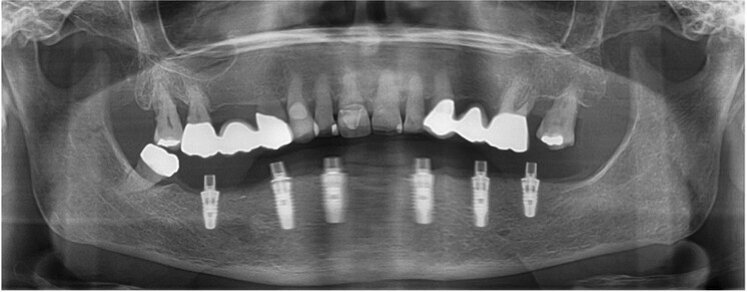

Fig. 1: Panoramic radiograph of the initial dental status.

The dental status showed acceptable oral hygiene and some teeth with Grade III mobility (teeth #41, 31, 32, 18 and 28) and local periodontal problems, including horizontal bone loss (teeth #42, 41, 31, 32, 33, 18, 17, 27 and 28). Teeth #42 and 33 were healthy and not mobile. The alveolar crest in the lateral mandible area showed clinically a wide shape with thick keratinised mucosa. The initial panoramic radiograph revealed stable crestal bone in the lateral mandibular area (Figs. 1–3). Thus, in the lower jaw, the single-tooth prognosis was fair for teeth #47, 42 and 33, and hopeless for teeth #41, 31 and 32.[24]